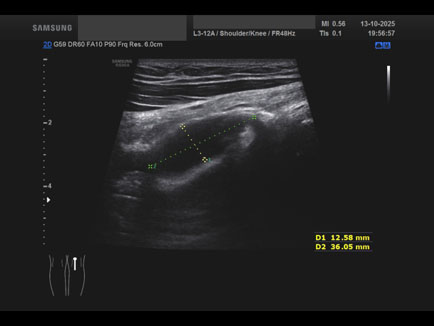

Data inserimento: 16/10/2025

Ecografia del: 13/10/2025

Strumento: Samsung

Sonda: Lineare

Commento all'esame: giovane atleta con referto di RMN che riporta cisti del semimembranoso/gemello e falda fluida lungo il gemello mediale medesimo.

Alla ETG:

A. formazione cistica di circa 22 x 17 x 23 mm (DAP x DT x DL = 4.5 ml) indovata tra il semimembranoso ed il gemello mediale: borsite dei tendini suindicati; assenza di falde fluide a carico dello sfondato sottoquadricipitale!

B. rottura completa del semitendinoso in sede distale con diastasi dei monconi di circa 25 mm.

Conclusioni: lesione e cisti del muscolo semitendinoso destro (right semitendinosus muscle injury and cyst).